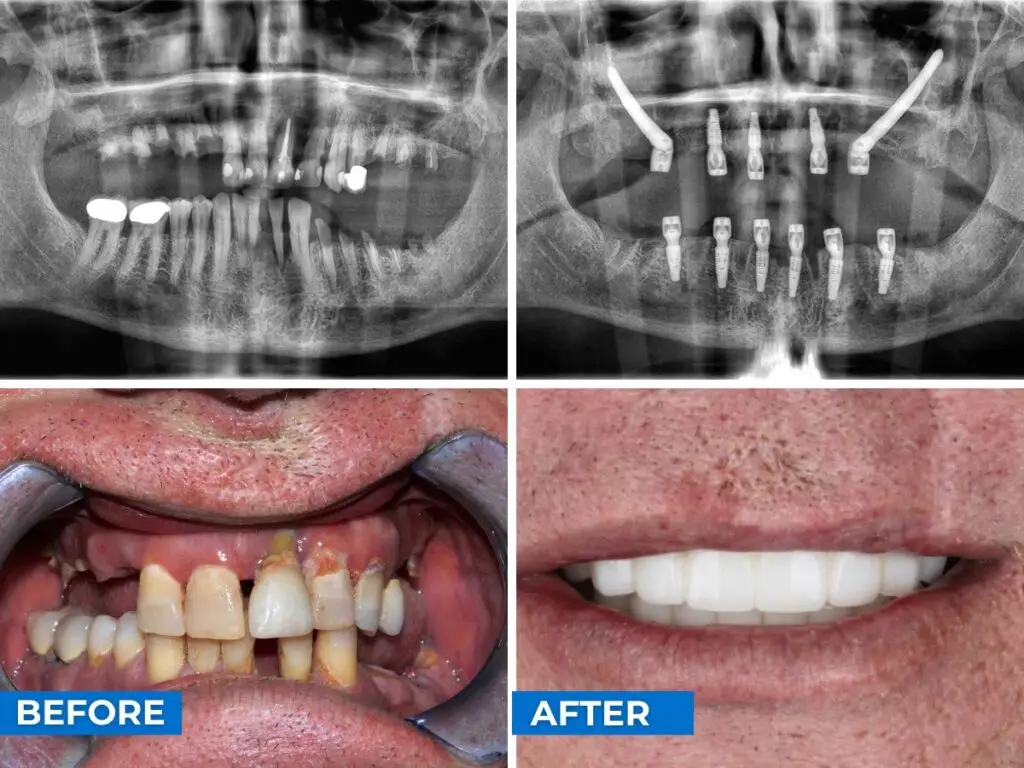

Transformaciones de dientes fijos en Cancún

El objetivo en Smile24h Expert Dental Clinic en Cancún es simple: devolver a los pacientes su calidad de vida. Los resultados del antes y el después muestran cómo los implantes dentales restauran no solo las sonrisas, sino también la confianza y la capacidad de disfrutar de la vida cotidiana nuevamente.